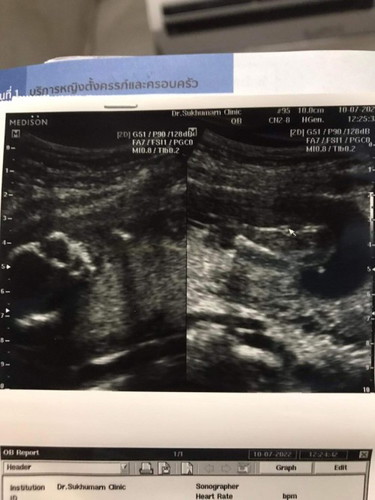

ทราบเพศลูกตอนกี่weekค่ะ ของแม่19weekแล้วซาวกี่ครั้งน้องหนีบตลอดเลยค่ะ 😂😂